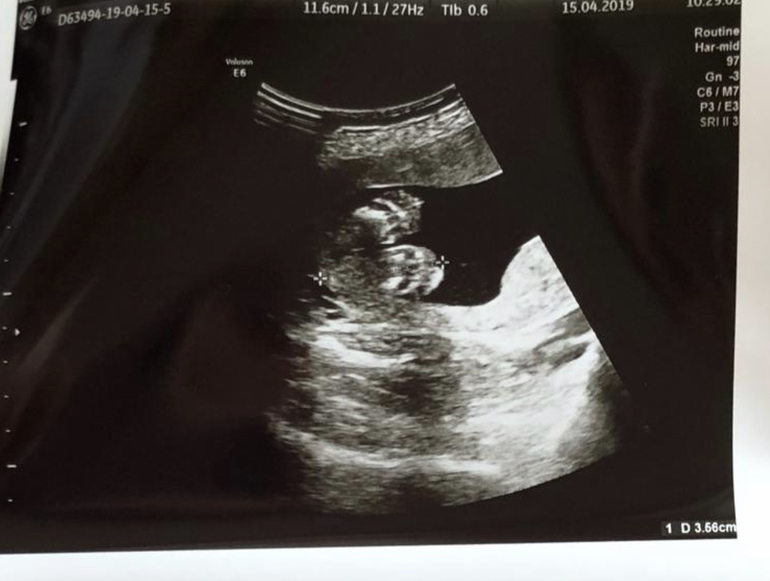

мы находимся в разных странах, поэтому и ситуации разные)) Тут даже по виду аппаратов видно - огромные, чистые, новенькие, мониторы прекрасные - огромный телевизор на стене, где мне видно моего кроху, да и снимки яркие, контрастные, так хорошо малыша видно, а в поликлинике у нас узиста специально для ЖК нет. По крайней мере в моей поликлинике

У нашего пупса размер стопы на втором скрининге 3.56см))

Спасибо ☺️ каждый раз очень волнительно - ждать эти узи) Прям облегчение вчера такое испытала что все хорошо! Думаю может у этих узистов глаз наметан и они все успевают смотреть "подиагонали"... Стопа действительно как будто великовата относительно размера всей ножки в целом, но писала по памяти, тк размер стопы не записали))) Может я что то путаю)) Но вроде как 3,5 см